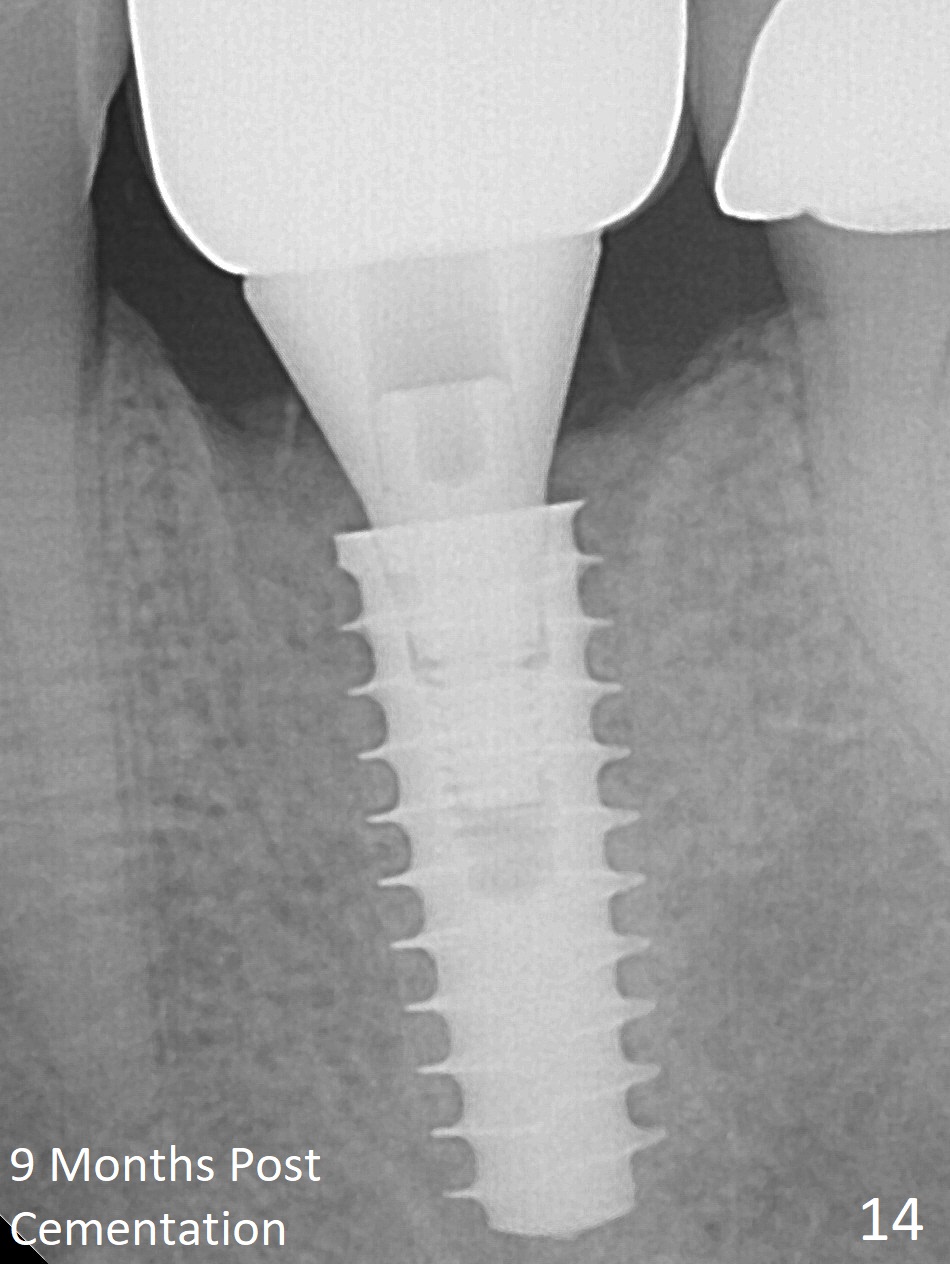

The gingiva looks healthy 8 months postop (3 months post cementation (after abutment screw retightening and addition of porcelain to proximal surfaces, Fig.12). New bone has apparently covered the implant plateau (Fig.13 arrows). Bone density between threads increases 9 months post cementation (Fig.14). There is 2 mm bone superior to the implant plateau mesial and distal 1 year 9 months post cementation (Fig.15,16). The crown/abutment is loose 3 times (3 months (Fig.14), 11 months (between Fig.14 and 15) and 2 years 3 months post cementation). In spite of being stable 3 years 10 months post cementation, a smaller abutment is placed (Fig.17 (PA), 18 (BW)) with impression for a new crown. After intraoral cementation, the new crown/abutment is removed for residual cement removal. When the complex is reseated, it is not smooth, probably due to proximal undercut. Fortunately the abutment appears to be completely seated, followed by 20 Ncm torque (Fig.19).